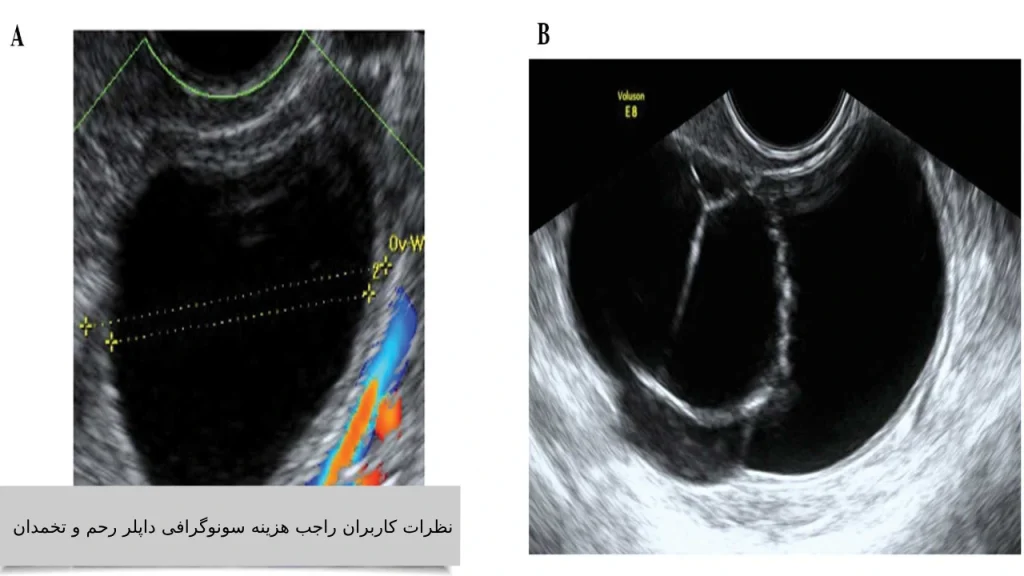

نظرات کاربران راجب هزینه سونوگرافی داپلر رحم و تخمدان

- سمیه رستمی – “من از طریق توصیه پزشکم با کلینیک ویستان آشنا شدم. سونوگرافی داپلر رحم رو اونجا انجام دادم، دستگاه خیلی دقیق بود و گزارش کامل دادن. قیمتش هم نسبت به جاهای دیگه خیلی مناسب بود.”

- الهام کاظمی – “تجربه خیلی خوبی داشتم. هم وقتدهی سریع بود، هم هزینه سونوگرافی داپلر رحم و تخمدان نسبت به خدماتی که گرفتن واقعاً منصفانه بود. ویستان رو به همه پیشنهاد میکنم.”

- ناهید احمدی – “برای بررسی کیست تخمدان رفته بودم داپلر بگیرم. هم محیط کلینیک ویستان تمیز بود، هم خانم دکتر خیلی باحوصله توضیح دادن. بیمه تکمیلی هم قبول کردن، هزینه برام خیلی پایین افتاد.”

- پریسا ملکی – “با اینکه ویستان خصوصی بود، ولی هزینه سونوگرافی داپلر رحم و تخمدان با مراکز دولتی تفاوت زیادی نداشت. کیفیت سونوگرافی خیلی بالا بود. از ویستان کاملاً راضیام.”

- مریم صادقی – “بار اولم بود سونوگرافی داپلر انجام میدادم. از برخورد پرسنل ویستان تا دقت گزارش همهچی عالی بود. خوشحال شدم که بیمه تکمیلیمو هم قبول کردن.”

- آزاده فتحی – “نسبت به مرکز دیگهای که قبلاً رفتم، ویستان خیلی بهتر بود. هم هزینه مناسبتر بود، هم جواب رو دقیقتر و سریعتر دادن.”

- ندا محسنی – “پزشک زنانم ویستان رو پیشنهاد داد. از نظر قیمت واقعاً منصفانه بود و با بیمه هزینهاش خیلی کمتر شد. به همه دوستام هم معرفی کردم.”

- رعنا یوسفی – “من تهران زندگی میکنم و قبلاً تجربههای خوبی از سونوگرافی نداشتم. ولی ویستان خیلی حرفهای بود. هزینهاش هم با اون کیفیت، کاملاً ارزش داشت.”

- شکوه سادات موسوی – “توی دوران بارداری مجبور شدم چند بار سونوگرافی داپلر انجام بدم. هر بار کلینیک ویستان رفتم چون خیالم راحت بود از هم قیمت هم کیفیت.”

- زینب قاسمی – “به خاطر خونریزی غیرطبیعی داپلر رحم نیاز داشتم. ویستان سریع وقت داد و با کمترین هزینه و بهترین برخورد کارمو راه انداخت. ممنونم ازشون.”